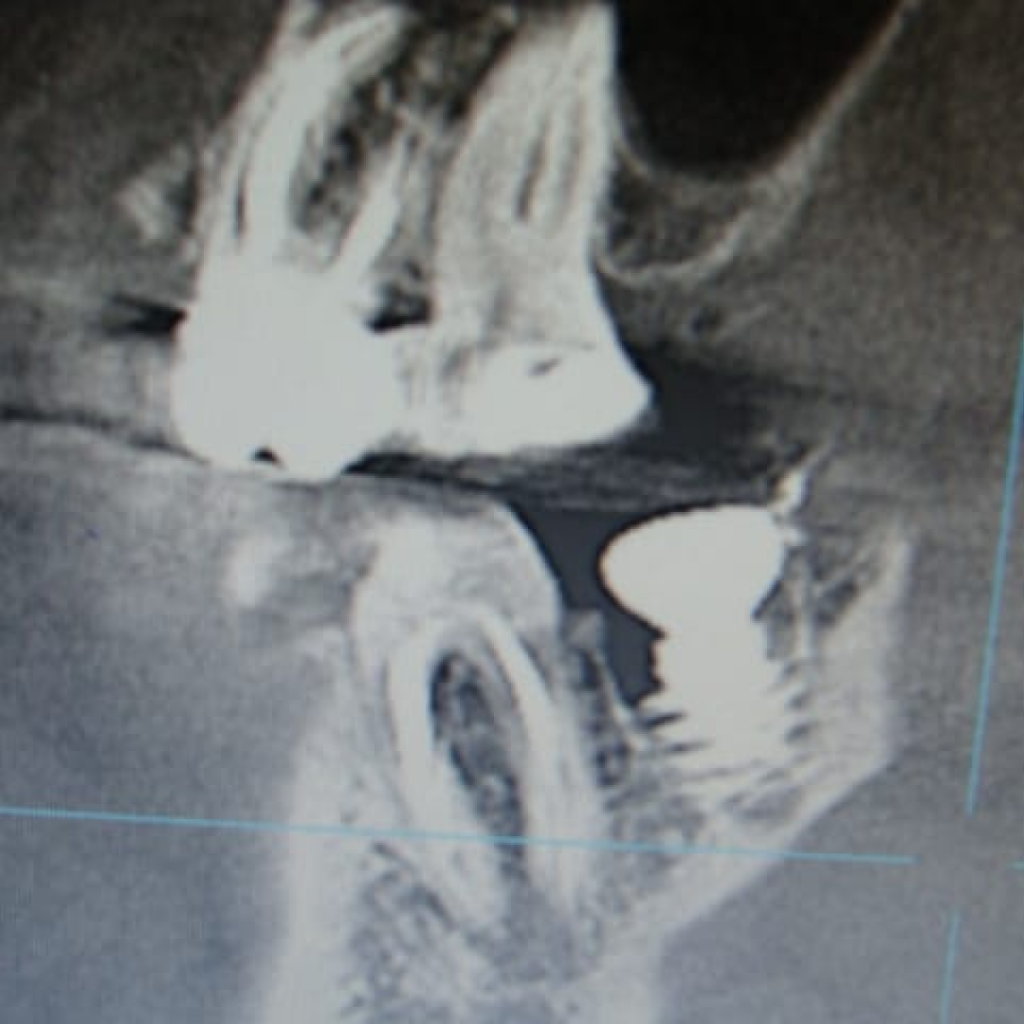

Особенности анатомии зубов после удаления составили:

- сросшиеся медиальный и дистальный корень

- отсутствие межкорневой перегородки

- диаметр лунок более 11 мм